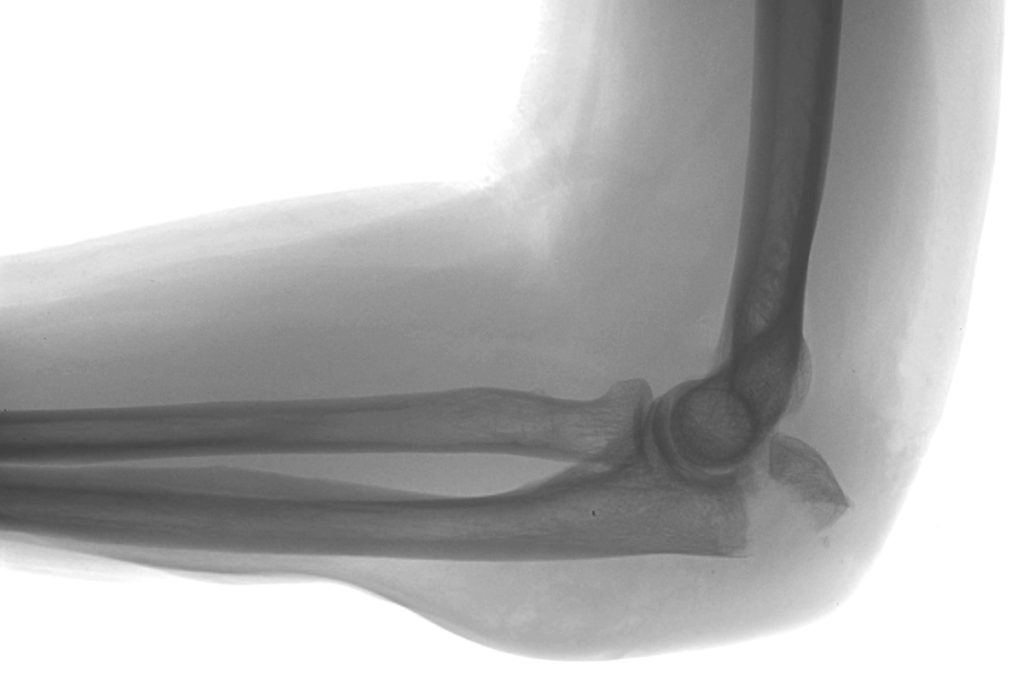

Displaced medical epicondyle fractures account for about 10% of pediatric elbow injuries, most commonly affecting children aged 10-12 years. These fractures are frequently associated with elbow dissociation. Management of this condition remains challenging, with non-operative treatment or surgical fixation. Most existing studies support both approaches, but high-quality evidence is limited. A recent SCIENCE study published in The Lancet aimed to evaluate whether surgical fixation improves functional outcomes compared with non-surgical care in children with displaced medical epicondyle fractures and to assess the cost-effectiveness of surgical treatment.

In conclusion, this SCIENCE trial suggests that surgical fixation for displaced medical epicondyle fractures in children should not be routine. Non-surgical care is preferred, cost-effective, aligns with patient preferences, and carries a lower risk of secondary procedures. Surgery should be reserved only for exceptional cases.